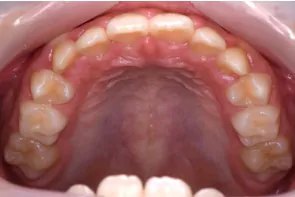

拡大床で対応できる症例

拡大床の症例

症例の概要

患者さんは7歳の女の子で、下の永久歯が2本生えた状態で叢生(ガタガタ)を認めました。

このままでは永久歯が正常に生えない為、拡大床でアーチを広げ前歯4本がしっかり生えるように矯正しました。

拡大床は1日16時間装着していただき、真ん中に見える装置を5日に1回、回してもらい拡大していきました。

治療期間は1年半でしたが、この期間は前歯がしっかり生えそろうまで、確認する必要があります。